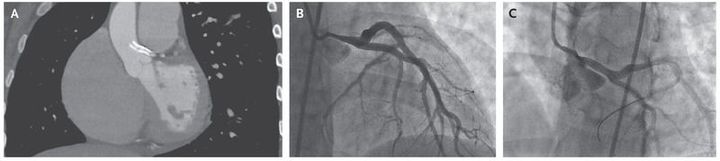

A 22-year-old woman with primary pulmonary hypertension presented with displacement of stents that had been implanted in the left main coronary artery and had migrated into the aorta (Panel A). She had been referred to our center for evaluation for lung transplantation. Her initial presentation to the referring hospital, more than 12 months earlier, had included recurrent chest pain and fainting spells. An angiogram was obtained at that time and showed stenosis of the left main coronary artery that was probably due to external compression from an enlarged pulmonary artery (Panel B). The patient underwent percutaneous coronary intervention, and two drug-eluting stents, measuring 8 mm×4 mm and 4 mm×4 mm, were placed (Panel C). The likely cause for the current presentation of displacement of these stents was compression from the enlarging pulmonary artery, with pulmonary-artery pressures close to 120 mm Hg. Given the complexity of the lesions and the location of the stents, it was decided that removal of the migrating stents and further angioplasty of the lesions presented undue risk. The patient was listed for combined heart and lung transplantation, which she subsequently received. At follow-up 1 year after transplantation, she was doing well.